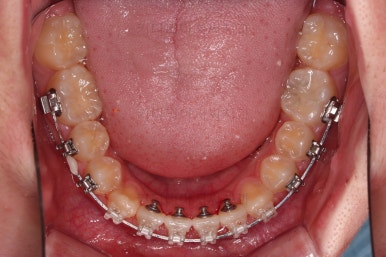

동래교정치과 초진 시 입안의 모습입니다.

치아가 벌어진 것도 벌어진 것이지만 교합이 전혀 안되고 있었어요.

틈새도 아랫니에 훨씬 많았고요.

윗니가 있는 위턱뼈가 전반적으로 아래턱에 비해 3차원으로 작은 양상이었습니다.

이번 환자분은 아랫니가 전반적으로 앞이든, 뒤든, 양옆으로든 넓어져 있는 양상이었고 그래서 아랫니에 틈도 많고 아래 앞니도 밀려나와 있는 양상인거죠.